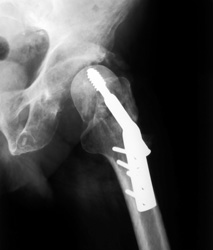

La CT è una sofisticata tecnica di imaging che ricostruisce un'immagine tridimensionale da numerose "fette" di immagini di un materiale. Il materiale viene poi rappresentato tramite voxel, piccole unità di volume che permettono una rappresentazione dettagliata della topologia e della geometria del materiale. Lo sfruttamento commerciale delle immagini di CT per la progettazione strutturale di biomateriali e impianti è attualmente ostacolato dalla mancanza dei corrispondenti dati fisico-chimici per finalizzare modelli meccanici FEM (degli elementi finiti). I bioingegneri utilizzano invece analisi di regressione o supposizioni basate sull'esperienza, facendo deduzioni piuttosto inadatte alla progettazione assistita da computer (CAD). Ricercatori all'avanguardia hanno recentemente sviluppato nuove tecniche per estrarre i dati sulla composizione chimica dalle scansioni CT e convertirli in proprietà dei materiali. Scienziati finanziati dall'UE hanno sfruttato queste conoscenze per sviluppare strumenti di simulazione per l'ortopedia e l'ingegneria dei tessuti ossei con il progetto BIO-CT-EXPLOIT(si apre in una nuova finestra) ("Innovative simulation tool for bone and bone biomaterials, based on enhanced CT-data exploitation"). In particolare I ricercatori cercavano una soluzione per la rappresentazione delle proprietà specifiche dei pazienti in un pacchetto software intuitivo e di facile uso, per aiutare I medici nella pianificazione degli interventi. Le scansioni CT di numerosi materiali ossei bio-ingegnerizzati e naturali con un esame meccanico completo dei biomateriali ha facilitato lo sviluppo di algoritmi per la conversione di informazioni volumetriche voxel-specifiche ottenute tramite raggi X in tre diversi tipi di proprietà elastiche. Queste sono state combinate con strumenti di analisi delle immagini per formare il pacchetto software completo. Il software di simulazione BIO-CT-EXPLOIT è un prezioso strumento per I medici, che permette una migliore pianificazione chirurgica e la personalizzazione di impianti e scaffold dei tessuti per I singoli pazienti. Ci si aspetta durate maggiori e minori complicazioni: un risultato particolarmente importante per la popolazione dell'UE che continua a invecchiare. Un'accurata conversione dei dati CT in proprietà meccaniche troverà senza dubbio applicazione anche in numerosi altri settori della ricerca sui materiali.